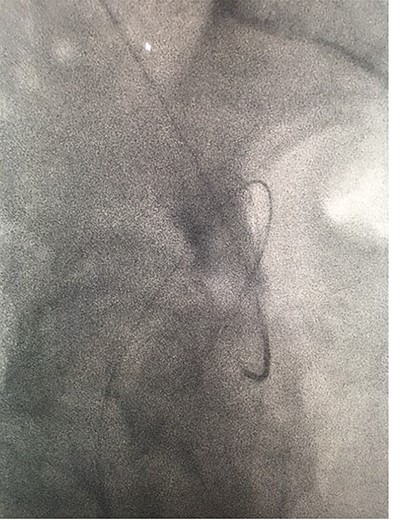

Under conscious sedation, using the previously inserted right percutaneous nephrostomy, antegrade access was achieved into the intrarenal collecting system and then into the proximal ureter. An 8 Fr × 11-cm access sheath was introduced. A guidewire was advanced antegradely through the site of ureteric transection and coiled in a position adjacent to the position of the guidewire that had been inserted retrogradely. A Gooseneck snare catheter was then passed over the guidewire and the snare was inserted (Figs 4 and 5). Under fluoroscopic guidance, the retrograde wire was retrieved and brought externally via the nephrostomy site, achieving through-and-through wire access (Figs 6 and 7).

Fluoroscopic images showing the antegrade Amplatz gooseneck snare catheter attempting to grasp the retrograde wire.